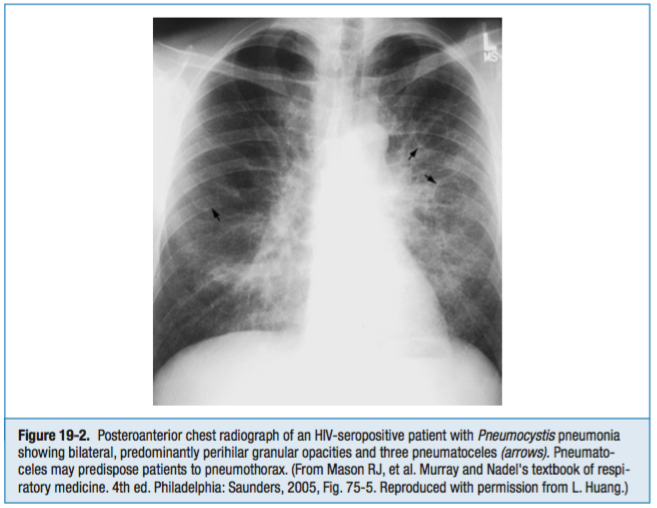

For the Step 2 examination, think of PCP first in any patient with HIV and pneumonia, even though community-acquired pneumonia is more common even in patients with AIDS.

Symptoms: dry, nonproductive cough

Diagnosis:

Treatment: TMP-SMX with corticosteroids